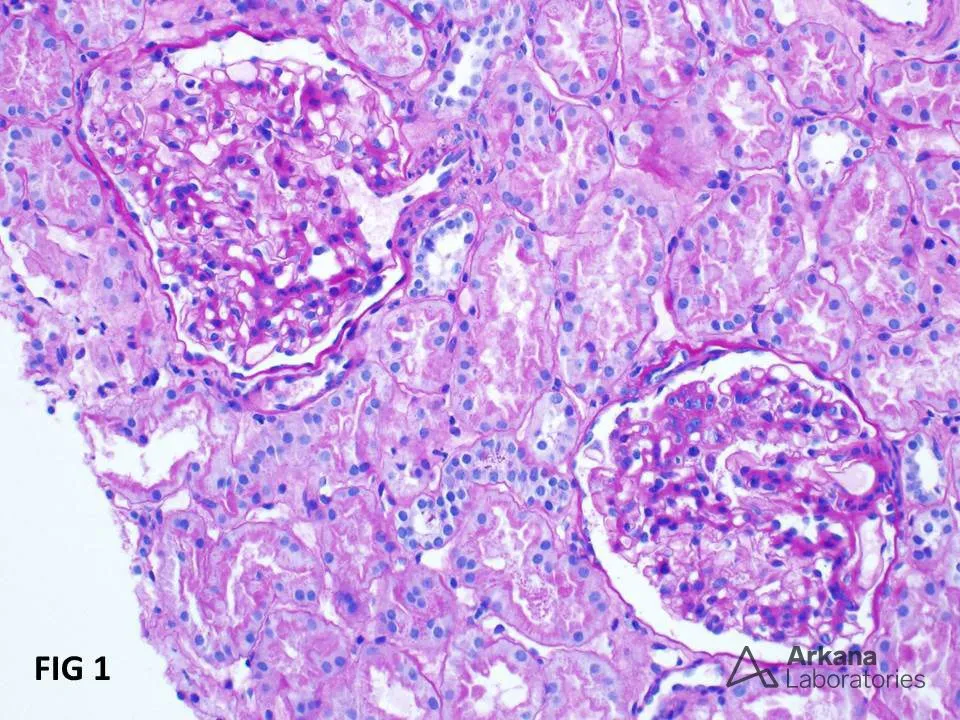

Diálise Peritoneal na Doença Renal Policística: existe algum motivo para não indicar?

Diálise Peritoneal na Doença Renal Policística: existe algum motivo para não indicar?

A DRPAD não é contraindicação à DP — e, na prática, muitos pacientes têm resultados comparáveis à hemodiálise. O “porém” está na mecânica: rins/hepatomegalia podem reduzir tolerância a volumes, aumentar risco de hérnias e extravasamentos, e piorar desconforto respiratório. Com técnica adequada (cateter presternal ou lateral, volumes menores, cicladora noturna e decúbito supino), a maioria das barreiras é contornável. Neste post, revisamos quando a DP é ótima, quando exigir cautela e como ajustar a prescrição para segurança e qualidade de vida.